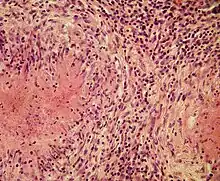

Structurally, epithelioid cells (when examined by light microscopy after stained with hematoxylin and eosin), are elongated, with finely granular, pale eosinophilic (pink) cytoplasm, and central, ovoid nuclei (oval or elongate), which are less dense than that of a lymphocyte.[4] They have indistinct shape and often appear to merge into one another, forming aggregates known as giant cells. When examined by transmission electron microscopy in epithelioid cells in the field of Golgi lamellar complex are taped not only zonated, but also sleek vesicles with dense center, and also great many (more than 100) large granulas with diameters up to 340 nm and with finegranular matrix more light than in macrophage granulas, sometimes with perigranular halo. “The most prominent feature of these cells is the enormous Golgi area; up to 6 individual stacks of Golgi cisternae may be present as well as a few bristle-coated and numerous smooth vesicles”.[5][4] Epithelioid cells have tightly interdigitated cell membranes in zipper-like arrays that link adjacent cells.[3] This cells are central in the formation of granulomas, which are associated with many serious diseases.[4] In granulomas, epithelioid cells perform the functions of delimiting.[3]